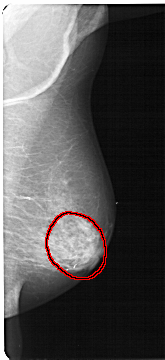

A_1302_1.LEFT_CC

FILE: A_1302_1.LEFT_CC.OVERLAY

TOTAL_ABNORMALITIES 1

ABNORMALITY 1

LESION_TYPE CALCIFICATION TYPE PUNCTATE-AMORPHOUS DISTRIBUTION REGIONAL

ASSESSMENT 4

SUBTLETY 3

PATHOLOGY BENIGN

TOTAL_OUTLINES 1

BOUNDARY